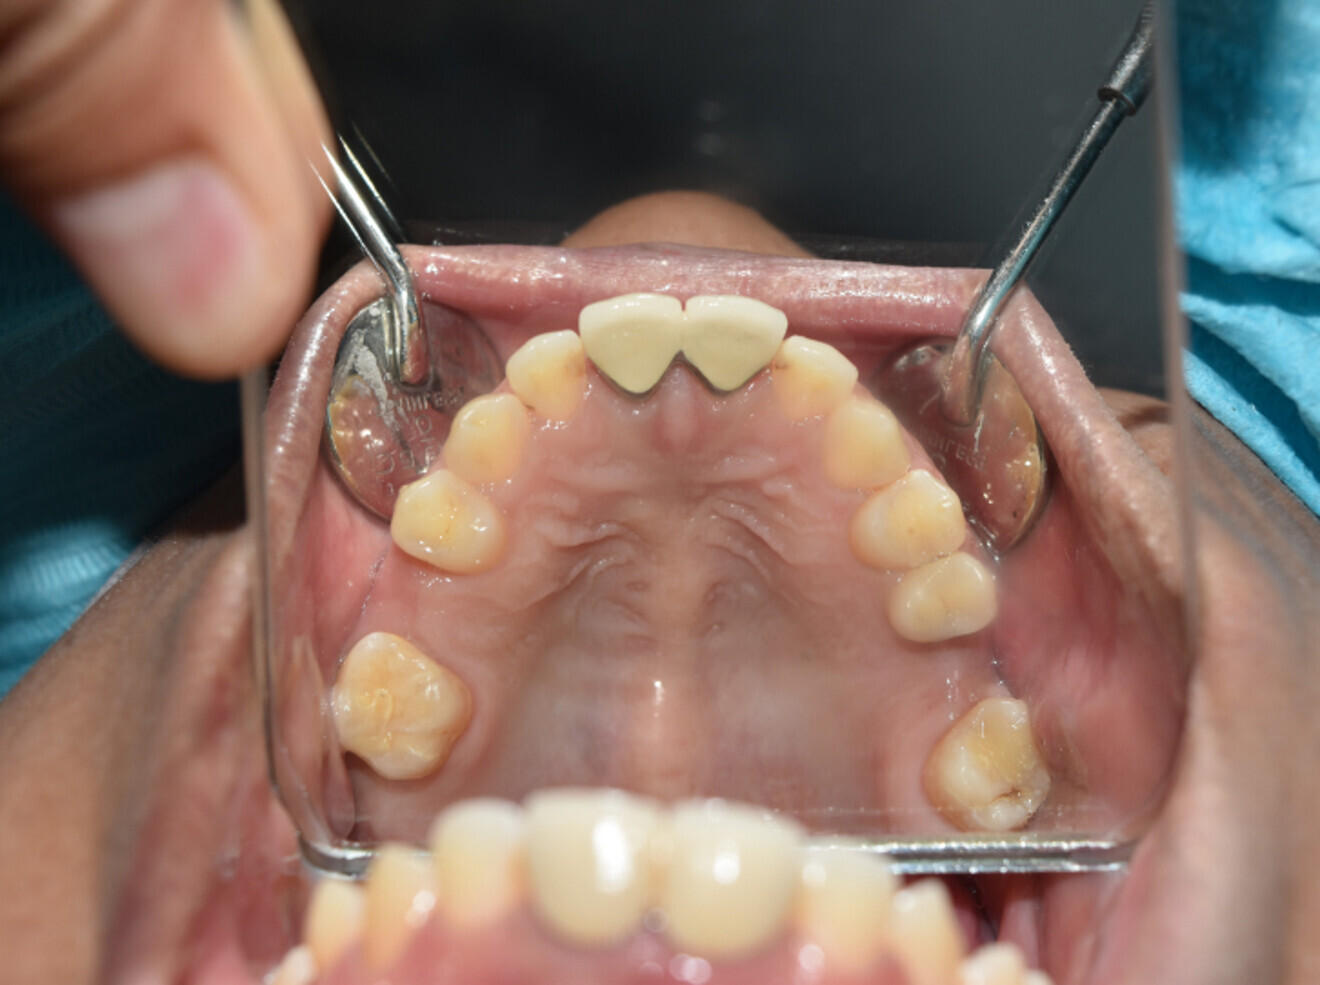

Case 1

• 64-year-old woman

• No underlying medical condition.

• Main complaint: Mobile upper front teeth. Big gap between upper centrals.

Intra-oral findings:

Class I malocclusion with poli diastemas in the upper anterior region.

Overbite= 2mm, Overjet= 2mm.

No molar classification (absence of molars).

Class I canine on right and left side.

Upper midline (mesial to 11) on with face.

Lower midline on with the chin.